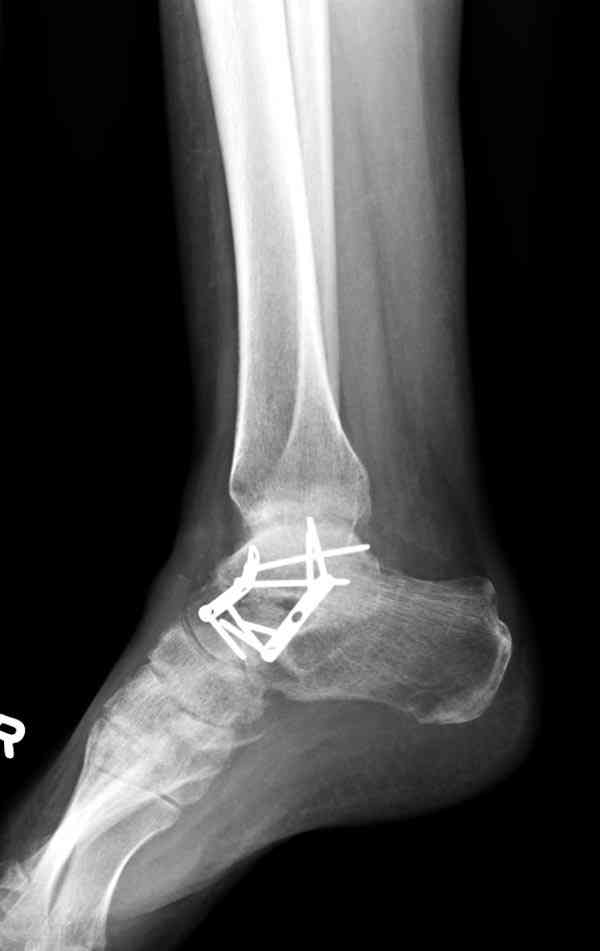

Случай с множественным оскольчатым переломом тарана оперированный из двойного доступа.

Через 2 мес.:

Через 8 мес.:

Через 14 мес.:

Два фрагмента суставной поверхности тарана можно восстановить боковой компрессией шурупами и дополнительно костная пластика.

(кстати, на нашем случае была применена костная пластика-allograft crouton для заполнения дефектов)

Наружный фиксатор "голень-пятка", "лигаментотаксис" при поступлении, домой через 48 часов после обучения ходьбы на костылях, в течение ближайшего времени осмотр в поликлинике для определения кондиции мягких ткани (тест на образование морщин в зоне разреза), при отсутствии отека примерно на 6-7 день с момента травмы операция.

Нагрузку можно разрешить через 2,5 месяца, на конечность снимаемый брейс удобен для разработки сустава которую можно начать после первичной перевязки.